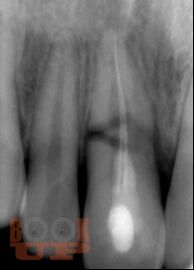

Представление материала сопровождается авторскими рисунками, фотографиями данными рентгенологических методов исследования, описанием клинических примеров.